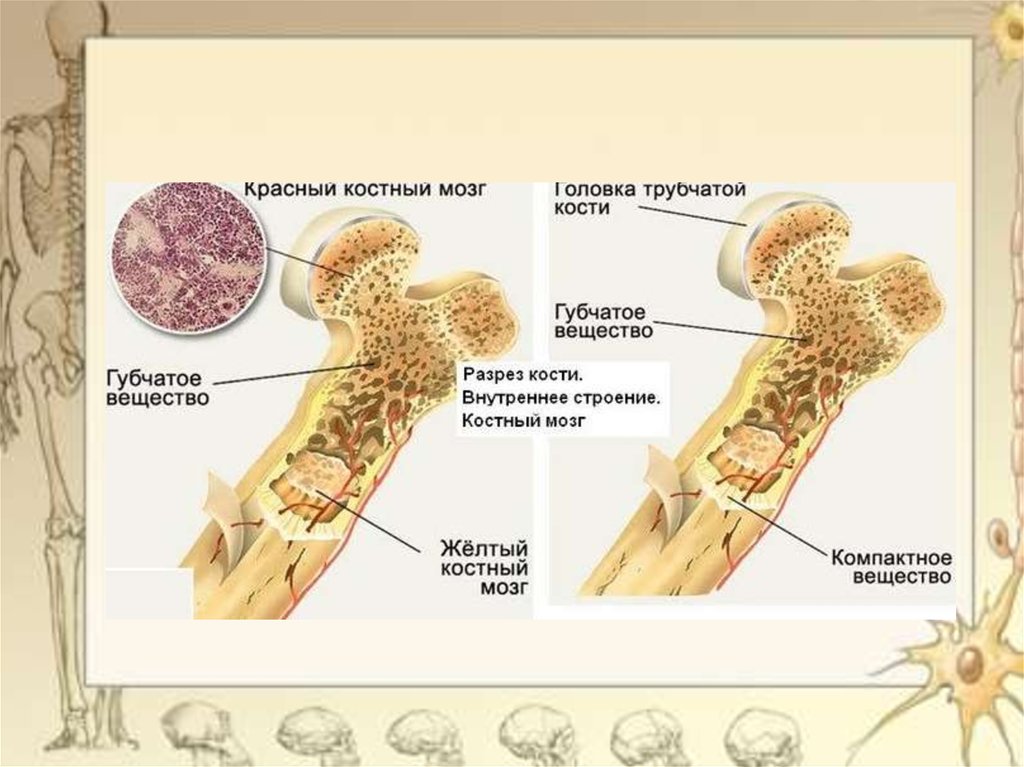

Изучение костного мозга: анатомия и функции